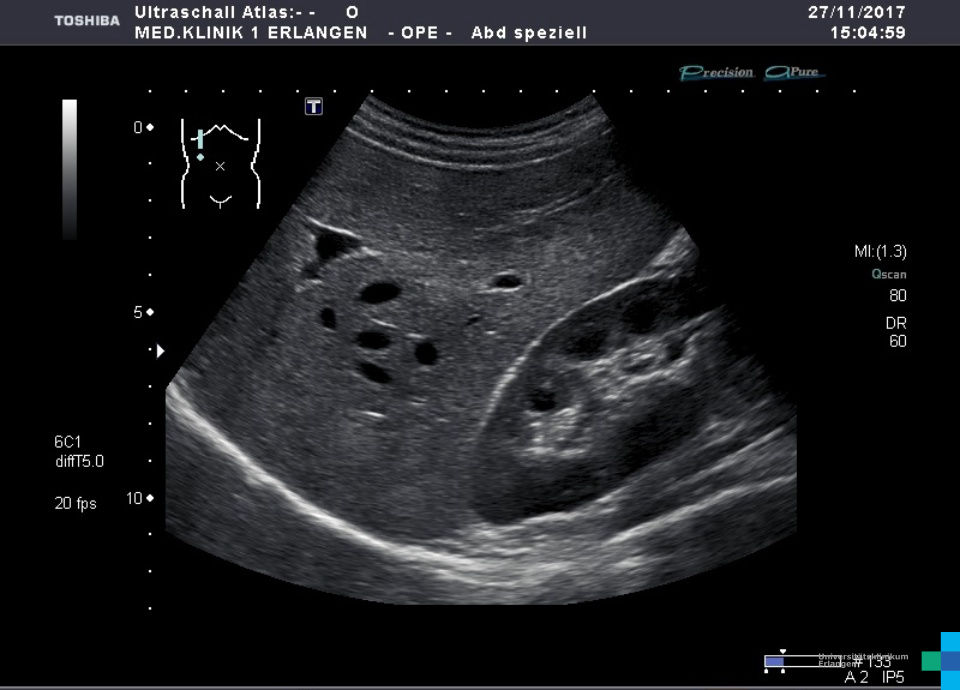

Normal liver – Atlas of Ultrasound